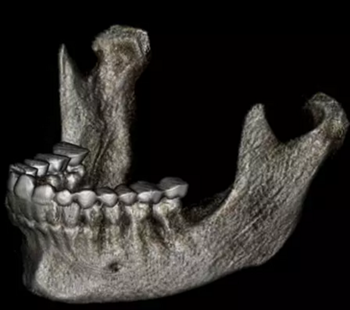

在輸出的3D模型上,使用體內(nèi)軟件(Anatomage,San Jose,Calif)將下頜骨以最小的間隔從顱骨上分離(圖5)用于保留下頜骨的咬合細(xì)節(jié),游離的下頜骨被保存(圖6,A)。同時,將沒有下頜骨的顱骨導(dǎo)出并保存(圖6,B)。

圖6. A,從整個3D模型上修剪的下頜骨; B,修剪的顱骨。